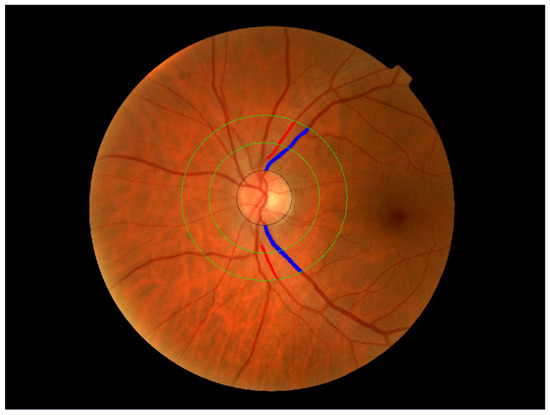

This Special Issue aims to highlight cutting-edge research, including but not limited to imaging advancements, new pharmacological interventions, and surgical innovations. Contributions exploring the clinical diagnosis and treatment of retinal diseases, such as age-related macular degeneration, diabetic retinopathy, and inherited retinal disorders, are encouraged. This Special Issue also seeks papers addressing the integration of artificial intelligence into diagnosis and management, as well as insights into patient-reported outcomes and quality of life.